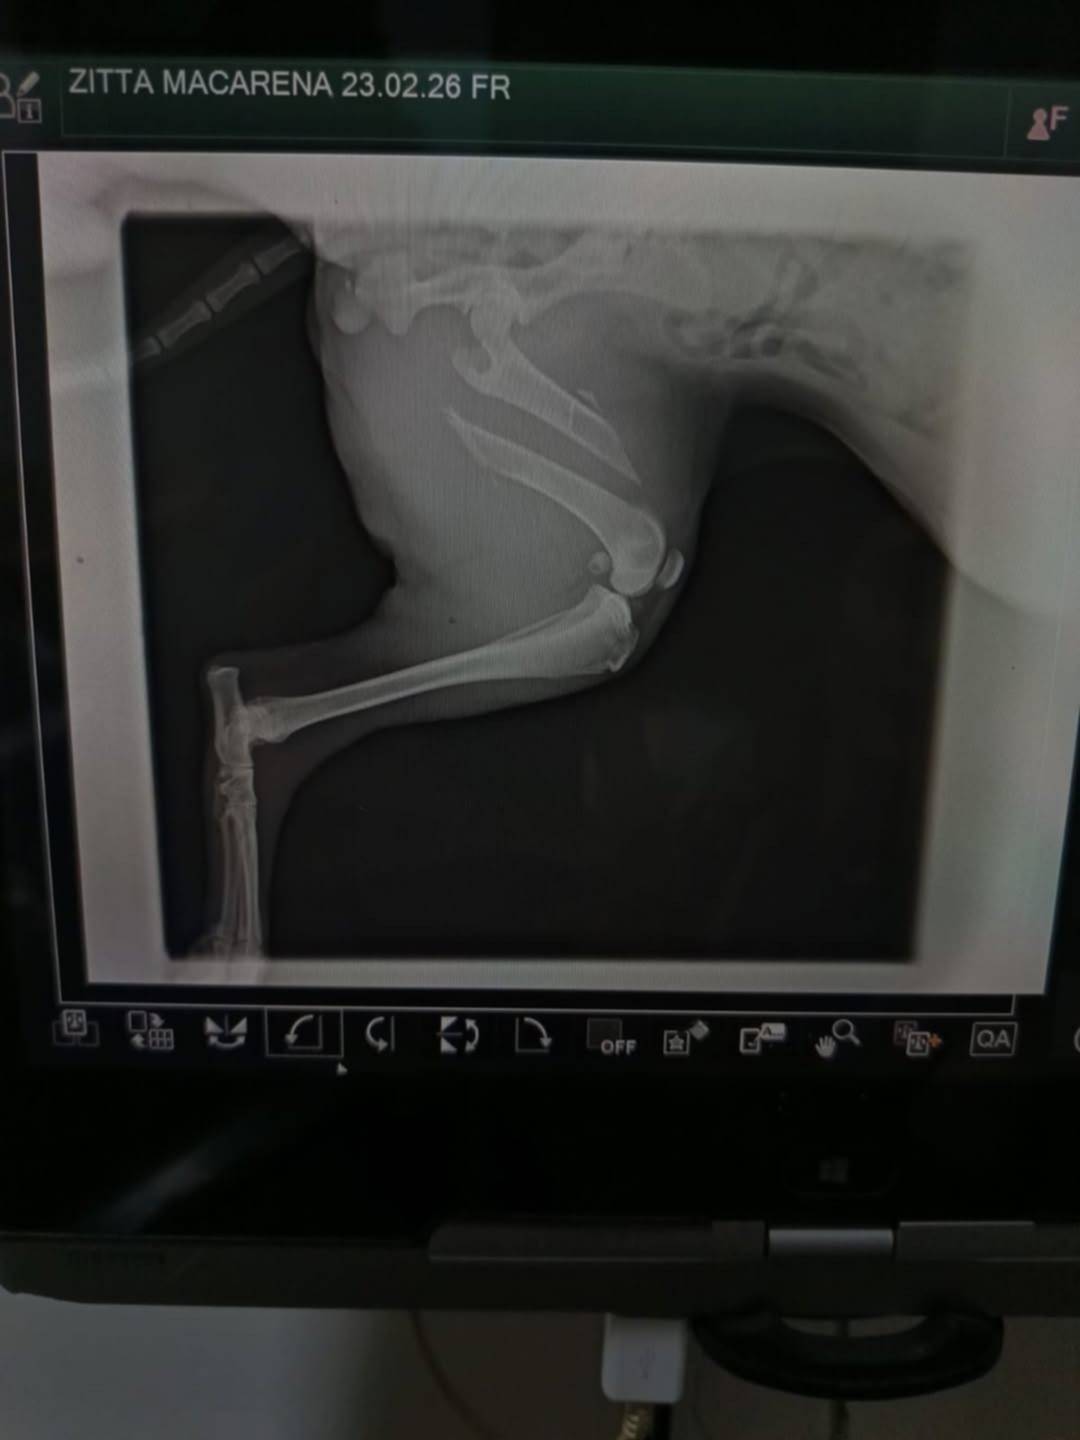

Durante el operativo rescataron a una perra que tenía una fractura expuesta que no había sido tratada, provocada por un atropello días antes. La herida se le estaba infectando a la vez que atraviesa un cuadro general delicado y bajo peso.